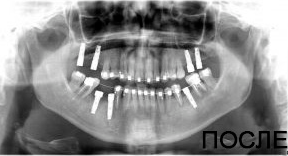

4 работы в портфолио

Удаления зубов любой сложности. Пародонтология (закрытый, открытый кюретаж, лоскутные операции, рецекция верхушки корня, вестибулопластика, френулотомия, френулоэктомия). Переостотомия, вскрытие абсцессов и других воспалительных процессов. Цистотомия, цистэктомия. Имплантология (установка имплантатов различных систем с осложненными анатомическими условиями, направленная костная регенерация, открытый синус-лифтинг, закрытый синус-лифтинг, пластика альвеолярного гребня).

Акопян Антон Владимирович: портфолио (4)